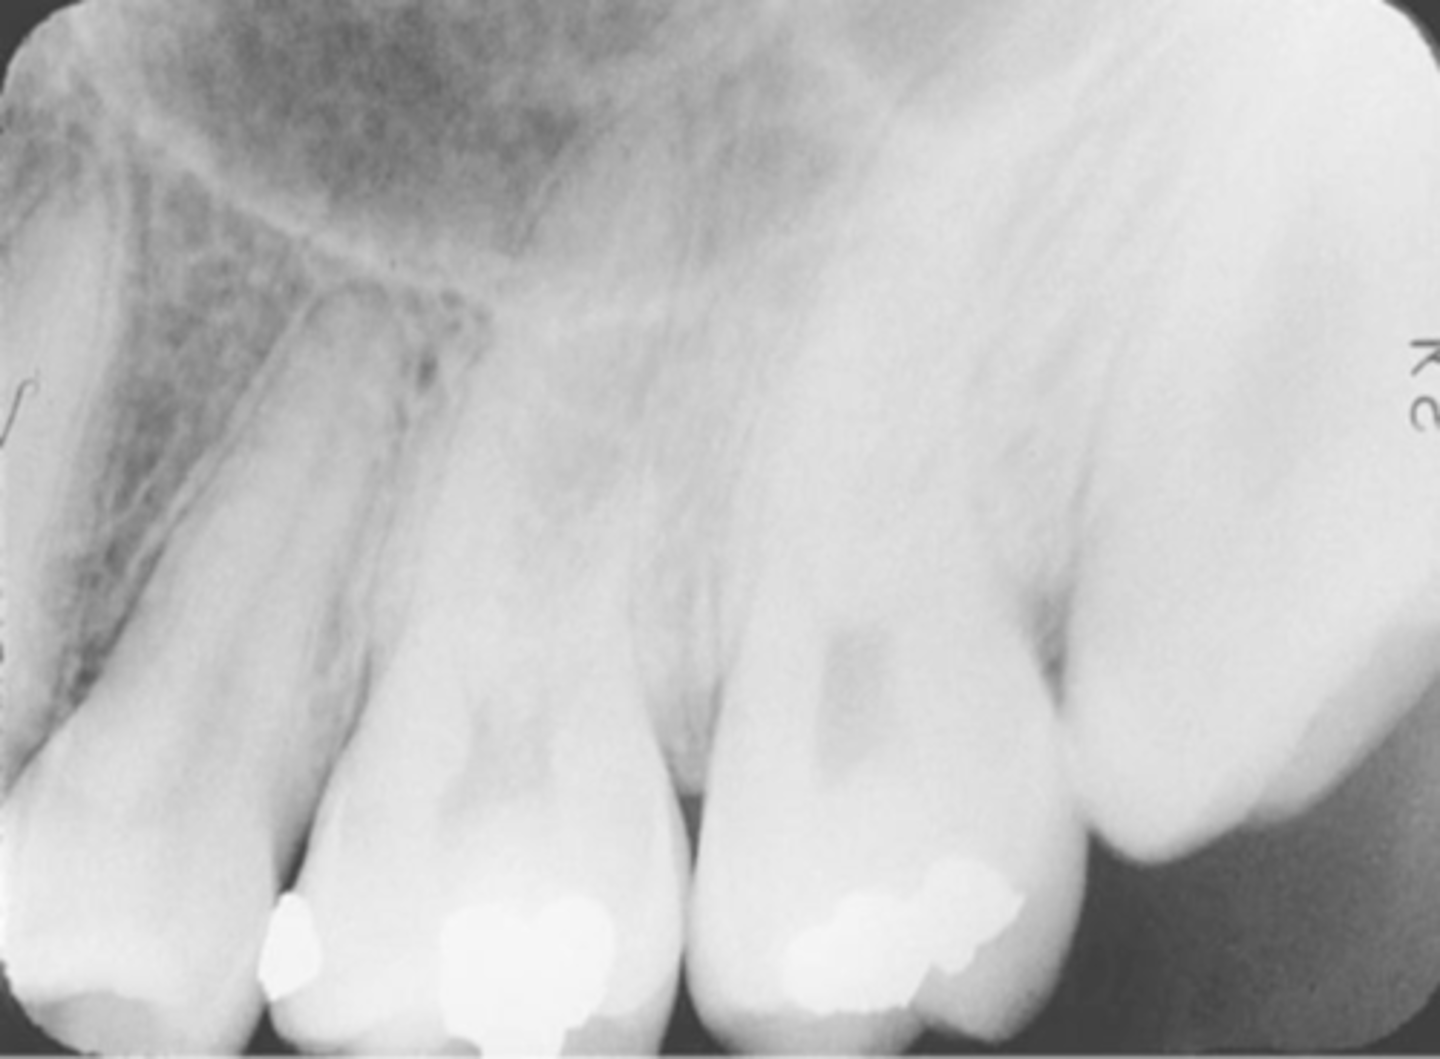

Overlapped Contacts

On a dental image, the area where the contact area of one tooth is superimposed over the contact area of an adjacent tooth

Incorrect Horizontal Angulation

-Overlapped contacts

-CR was not directed through the interproximal spaces, resulting in the proximal surfaces of adjacent teeth appear overlapped in the PA.

-Occurs in both paralleling and bisecting technique

-To prevent direct the x-ray beam through the interproximal regions

Incorrect Horizontal Angulation -->Bite-Wing

-CR was not directed through the interproximal spaces.